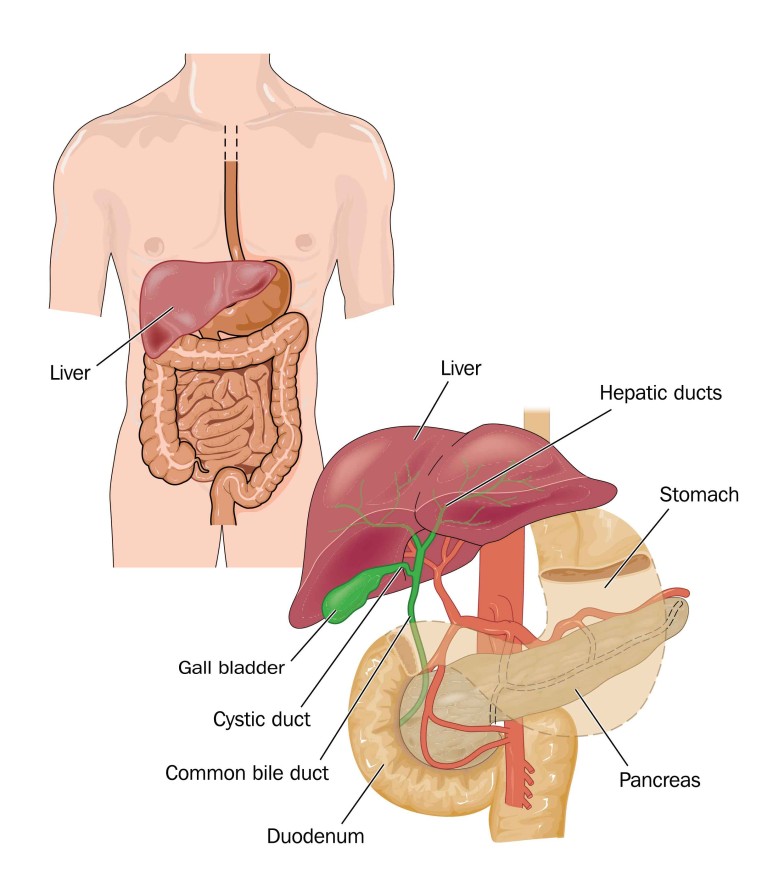

폐쇄성 황달이 나오는 원인은 담관이 막혀서 시작됩니다.

담관이 막혀 담관의 확장이 이루어지는데 처음에는 정상으로 보이는 경우가 있으나 시간이 지나면 문제가 발생합니다.

담관 담석과 양성 협착의 경우 보다 종양으로 인하여 담관이 막힐 경우 담관 확장이 더욱 심해집니다.

또한 담낭 관원위부의 총 담관이 막히는 경우 담즙의 압력 상승으로 담낭까지 확장될 수 있습니다.

그 원인이 총 담관 담석의 경우 담낭 확장이 이루어지지 않는 경우가 많은데 이는 완전 폐쇄가 아닌 부분 폐쇄로 담즙이 부분적으로 흘러나와 담낭 내의 압력을 높이지 않기 때문입니다.

또한 총 담관 담석의 유래가 담낭인 경우에는 담낭에 만성적인 염증이 동반되어 섬유화가 진행되어 담낭의 확장이 불가능하기 때문입니다.

따라서 신체검진시 손으로 만질수록 담낭의 크기가 커지고 있으나 압통이 없는 경우에는

이를 Courvoisier 징후라고 하는데, 담관폐쇄의 원인이 총담관석에 의한 것이 아니라 악성폐쇄일 가능성이 높습니다.

담관이 폐쇄되면 간에도 영향을 미칩니다.

담관주위 담즙유출, 문맥주위염증, 담관확장, 담전형성 등으로 간조직에 변화가 발생합니다.